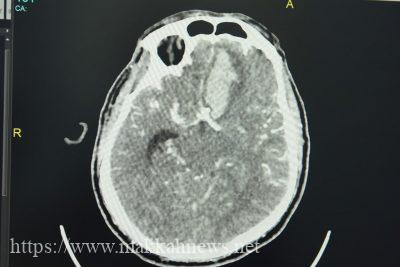

بفضل من الله تمكن فريق طبي من قسم جراحة المخ و الأعصاب بمستشفى شرق جدة من إجراء عملية جراحية نوعية في الدماغ لمريض يبلغ من العمر ( 61 ) عاماً و قد حضر المريض للطوارئ و هو في حالة صداع شديد و غثيان و قئ و فقدان جزئي للوعي و تم إجراء كامل الفحوصات اللازمة حيث أظهرت أشعة شرايين الدماغ نزيفاً حاداً بالفص الجبهي الأيسر للدماغ و نزيفاً بالسحايا كما أظهرت الأشعة وجود أم دم كبيرة الحجم في مسار الشريان الوصالي الأمامي ، و كان نزيف أم الدم نتيجة إرتفاع ضغط الدم مما أدى لظهور هذه الأعراض لدى المريض و قد تم إخضاع المريض لعملية دقيقة إستعجالية لإنقاذ حياته إستمرت لثلاث ساعات تم خلالها تفريغ النزيف الحاد داخل الدماغ و إغلاق ( أم الدم ) أو ( الأم الدامية ) بواسطة ملقط معدني و بذلك يكون قد تم فصلها عن الدورة الدموية و ذلك من خلال شق في الجمجمة أدخل من خلاله الملقط المعدني ، و كانت قد تمت هذه العملية الجراحية مع إتخاذ كافة الإجراءات الإحترازية لفرضية وجود إصابة بفيروس كوفيد 19 كما أوضح الإستشاري الذي قام بإجراء العملية الجراحية الدكتور منير إسماعيل بأن مثل هذه الحالات هي عبارة عن تشوه في بعض الاوعية الدموية في الدماغ مما أدى إلى كبر حجمها تدريجياً و أدى إلى تمدد جدران الكيس الدموي إلى أن تصبح رقيقة ما يجعلها عرضة للتمزق و النزف داخل أنسجة الدماغ أو حولها و خاصة عند إرتفاع ضغظ الدم فتسبب أعراض مفاجأة للمصاب منها الصداع الشديد جدًا و حدوث تصلب في الرقبة والشعور بالغثيان و القئ عدم تحمل الضوء في بعض الاحيان فقدان الوعي ، و يتم تشخيصها بواسطة أشعة الشرايين الدماغية و يحتاج المصاب عناية سريعة و متخصصة و تدخلاً جراحياً او علاج تداخلياً حسب الحالات